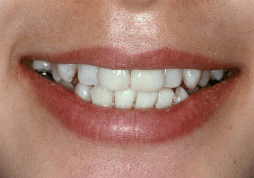

※写真は神経がない歯にブライトホワイトを一回行った写真です。右の前歯2本の神経がありませんが、歯の内部に汚れがなかったため、表からのホワイトニングだけでかなり白くなっています(詰め物は白くなっていません)。